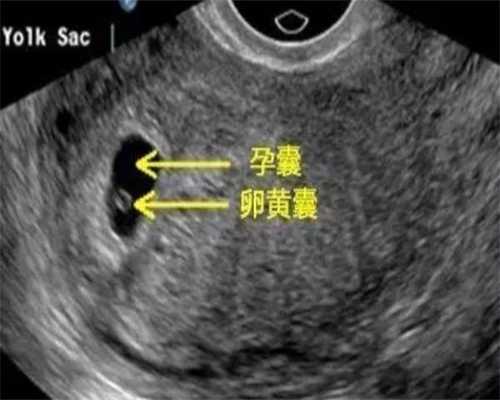

窦卵泡即基础卵泡也叫始基卵泡,是卵泡的发育始于始基卵泡到初级卵泡的转化。通过窦卵泡计数,可以对于成熟卵泡总数进行预测,从而便于预估试管婴儿的成功率。

在进周初期(一般是月经第二天),医生会通过B超看看你有多少个基础卵泡(窦卵泡),然后开始促排。在促排卵的过程中,药物会诱发多个卵泡同时发育,到了有卵泡成熟的时候确定取卵日期。